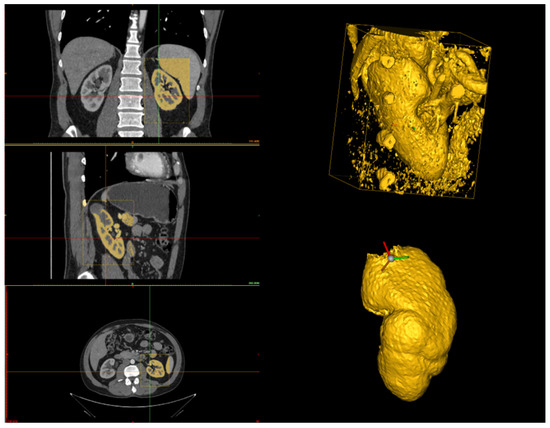

In this Section, we outline the segmentation protocol for obtaining accurate 3D reconstructions of organs and tumors. Our protocol is specific for the reconstruction of kidneys and their associated tumors. The main objective of the protocol is to describe how a human operator should proceed to segment the kidney and the tumor to ensure an accurate reconstruction. Therefore, we structured the protocol into three steps: kidney segmentation, tumor segmentation, and reconstruction refinement. After completing these steps, accurate 3D reconstructions were generated (see Figure 1) and exported as STL files. These files were then provided as input to our algorithm for calculating the CSA.

The human operator can set the HU range by choosing upper and lower bounds to highlight all the kidney structures and minimize cavities and holes in the kidney model (see Figure 2). Since the quality of the CT scan significantly influences the HU range, it is difficult to define a universal range. However, based on our experience with high-quality CT scans, the recommended range is (80–1969) HU. In the case of lower-quality scans, these limits can be adjusted to achieve an optimal reconstruction. Additionally, after setting these values, it is advisable to retain only large regions and automatically fill small holes. Once the segmentation of the region of interest (that is, a bounding box) is performed, the result is the 3D model of the kidney, together with other smaller parts from the surrounding tissues (see Figure 3).

Figure 3. On the left-hand side, the selection of the region of interest in the three planes (axial, coronal, and sagittal) is shown, where the region defined in yellow represents the kidney based on a threshold application. On the top right-hand side, the 3D reconstruction after the threshold application is displayed. On the bottom right-hand side, the 3D reconstruction after manual cleanup, where all surrounding structures have been removed, leaving only the kidney.